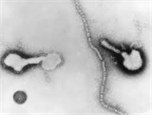

(바이러스) Human parainfluenza virus type 1, 2, 3, 4

출처:http://phil.cdc.gov/phil/details.asp ID#271, CDC/ Dr. Erskine Palmer

• 특 성 :Paramyxoviridae과, 1형과 3형은 Respirovirus속, 2형과 4형은 Rubulavirus속, (-)ssRNA, 외피 있음